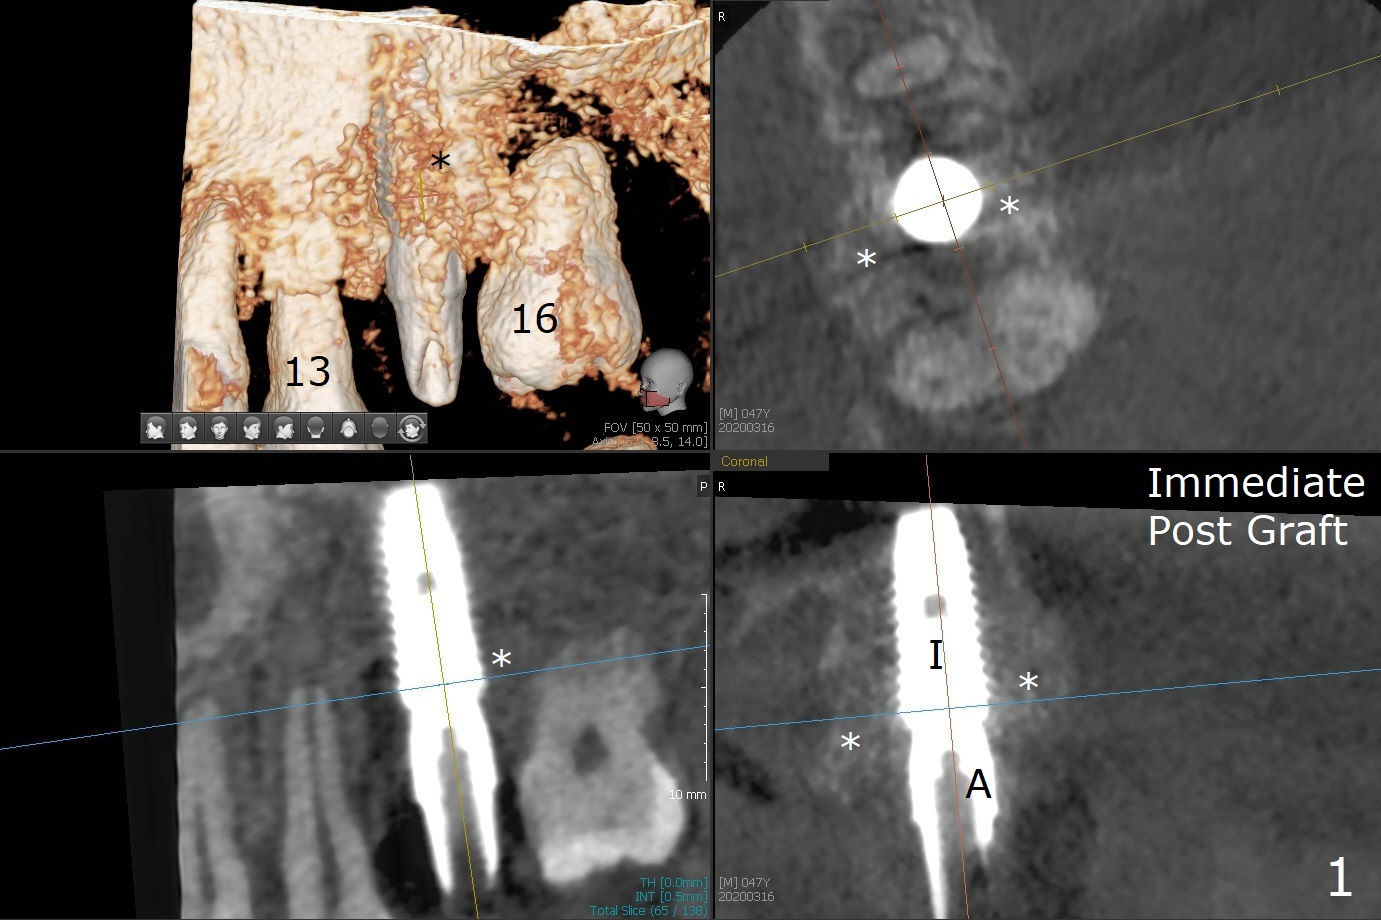

Access to the bony defect of #14 occlusally is limited due to #16 mesial incli-nation. Incision is made. After debride-ment, use of Round Brush, buccal plate decorti-cation and abutment retight-ening, sticky bone is placed around the exposure implant (I) threads and abutment (A) cuff amply (Fig.1,2 *). A piece of PRF membrane and 15x20 mm Vitala (Porcine Derived (peri-cardium) Collagen Membrane) are fixed in place around the abutment. The wound is closed with 4-0 PGA suture. The mobile teeth #12,13 and 16 are immobilized to #14 implant/abutment using acrylic as a wound dressing as well.